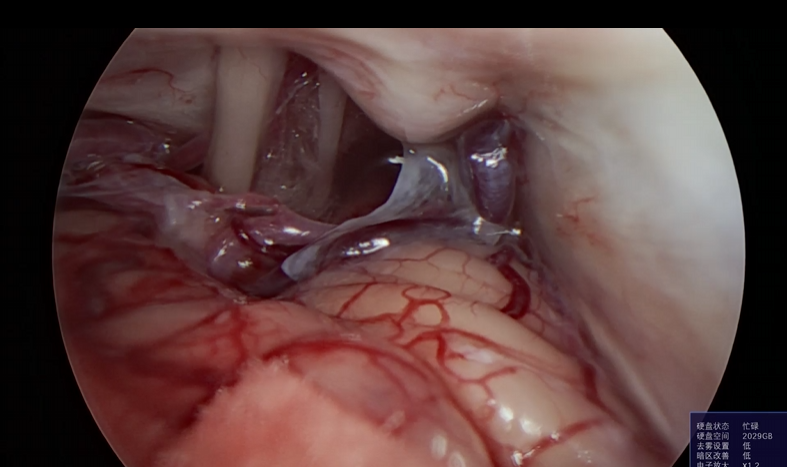

神经外科垂体瘤手术